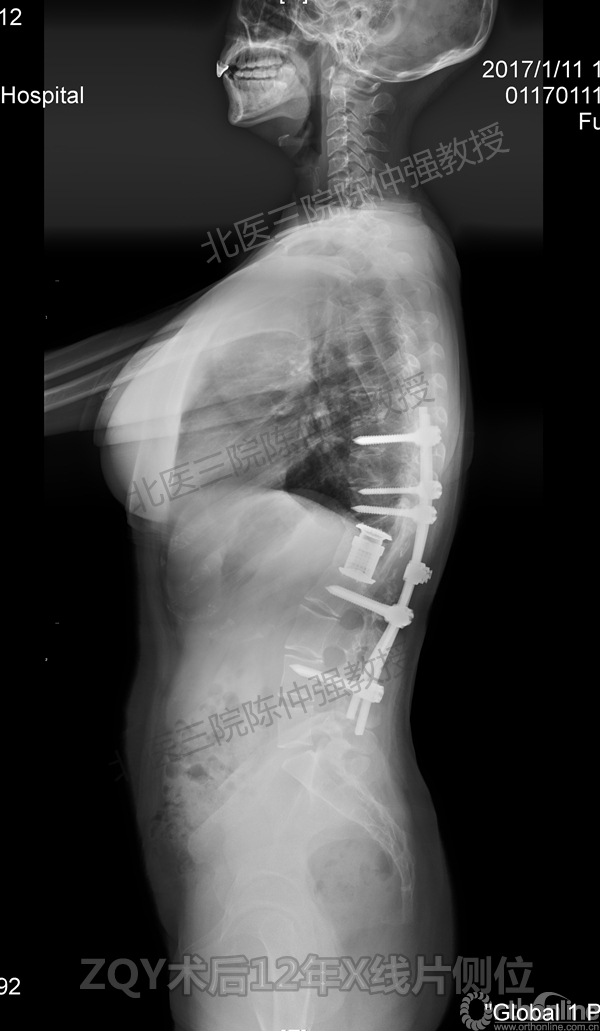

2005年,陈仲强教授在AOSpine年会上分享了一例胸腰椎陈旧结核性侧后凸畸形病例。资料如下:

患者女性17岁,胸腰椎陈旧结核性侧后凸畸形,局部呈“麻花状”扭转,无神经功能受损表现。2005年,陈仲强教授带领团队实施后路+侧前方联合入路脊柱节段切除、双轴旋转矫形术。术后患者外观显著改善,神经功能正常。术后随访证实患者截骨矫形节段骨性融合良好,矫形效果持续良好。